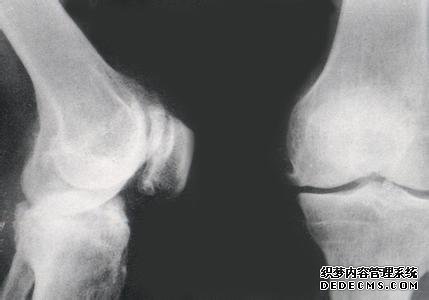

1、关节僵硬。在病情的早期,患者获得关节时可出现障碍,还会发出骨摩擦的咔咔声,以膝关节和髋关节比较明显。